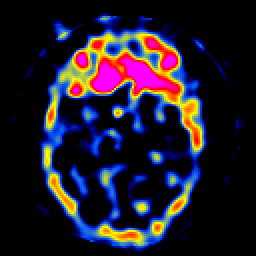

SPECT TL Study #8 -- Slice #20

[Home][Help][Clinical][Tour 1][Tour 2][Tour 3] Slice 20